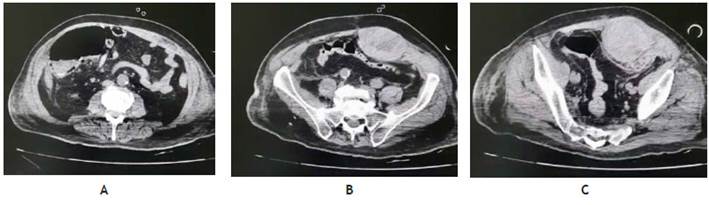

Durante la valoración clínica rutinaria del abdomen, se evidenció una masa dura en el cuadrante inferior izquierdo de bordes delimitados de 8 x 6 cm. El paciente no mostró manifestaciones clínicas abdominales ni sangrado digestivo, por lo que se decidió realizar un estudio tomográfico que reportó neumatosis en ángulo cólico derecho, neumatosis mesentérica y una masa palpada que correspondió a un hematoma de pared abdominal de 17,4 x 8,2 x 6,1 cm con un volumen aproximado de 452 cm3, que se atribuyó a la anticoagulación recibida (Figura 1).

Figura 1 TAC simple de abdomen con evidencia de (A) neumatosis en ángulo cólico derecho, (B) neumatosis mesentérica y (C) hematoma abdominal